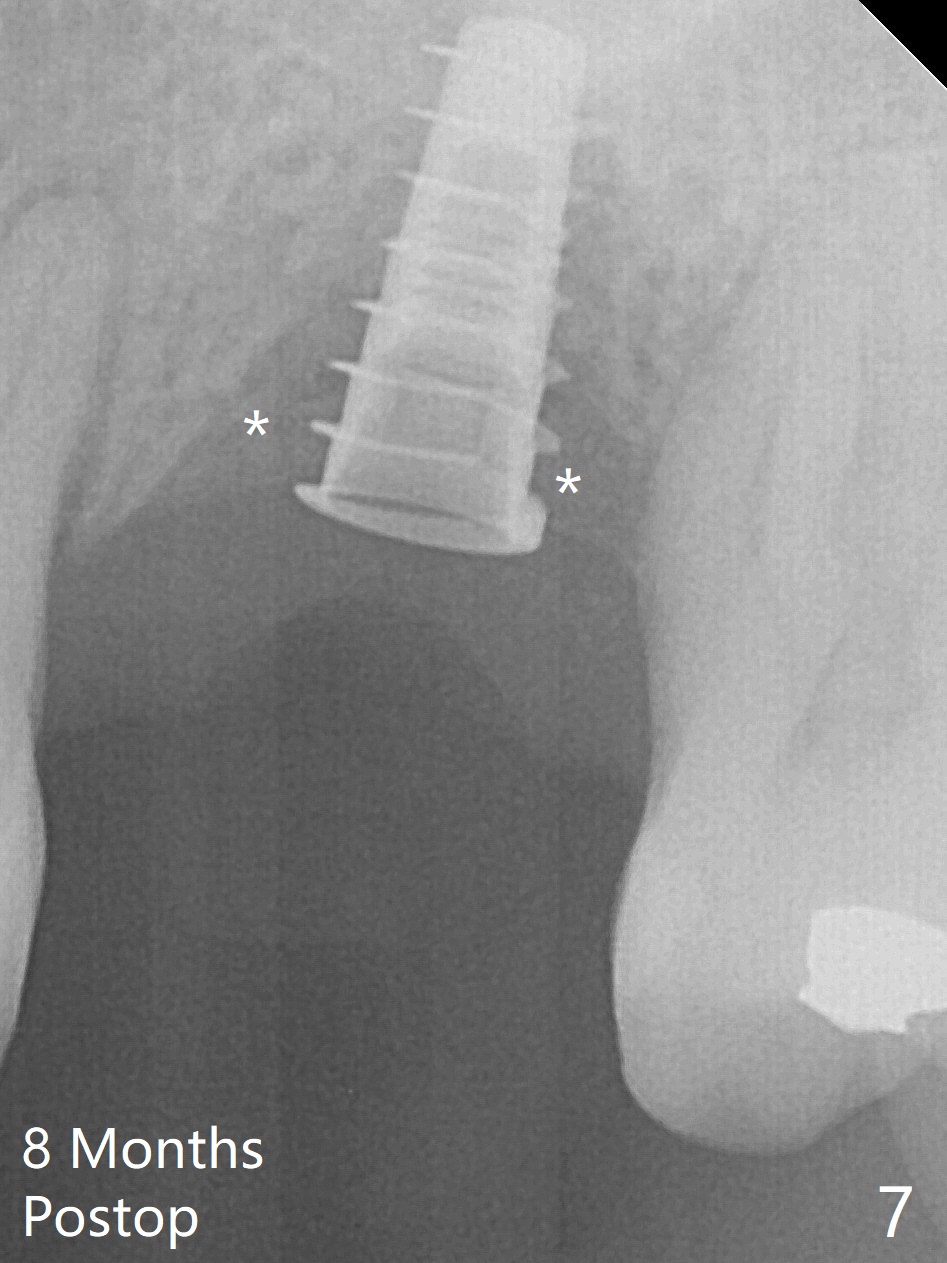

Preop exam shows the narrow ridge at #14. Magic split is used for access and initiation of osteotomy and bone expansion, followed by 3 mm Magic Expander for 11 mm (ME, Fig.1 (yellow line: sinus floor)). In fact the bone is soft. After use of 3.8 mm ME and Lindamann bur (to move the osteotomy distobuccally), a 4x11 mm dummy implant is placed with 20 Ncm (Fig.2). Following use of Lindamann bur for the same purpose as mentioned above, a 4.5x9 mm IBS implant is placed 3 mm subgingival with <30 Ncm (Fig.3,4). Bone graft is placed for sinus lift prior to implantation. A 5x3 mm healing abutment is placed. Bone loss is minimal 3.5 months postop (Fig.5) and striking 8 months postop (after crown cementation, Fig.6-8). The bone loss persists in spite of crown and abutment removal (Fig.9,10). Bone graft or implant redo is planned.